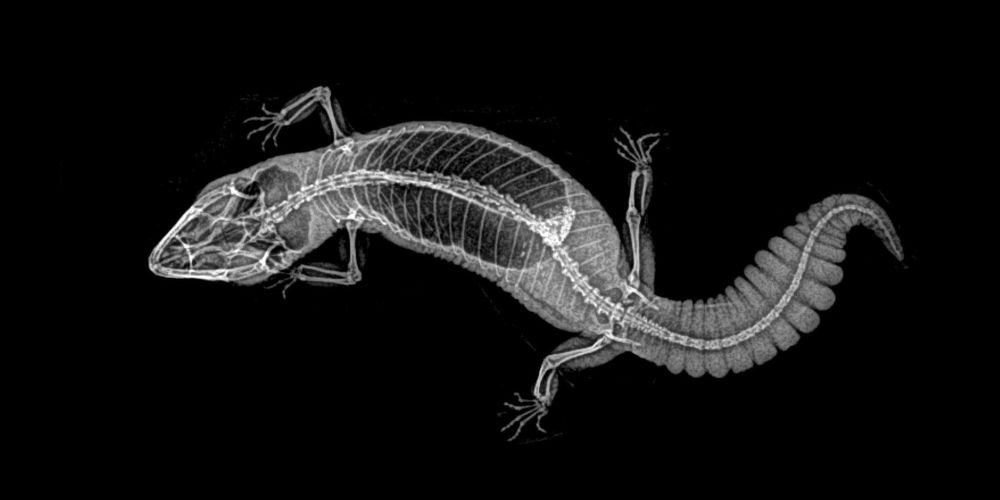

ABD'nin Oregon eyaletinde bulunan bir hayvanat bahçesi, hayvanların rutin sağlık kontrolleri sırasında çekilen X-Ray görüntülerini paylaştı.

Sağlık kontrolleri sırasında bazı hayvanlara röntgen çektiklerini söyleyen hayvanat bahçesi yetkilileri, bu yöntem sayesinde sağlık değerlendirmelerinin daha kolay yapıldığını ifade etti.